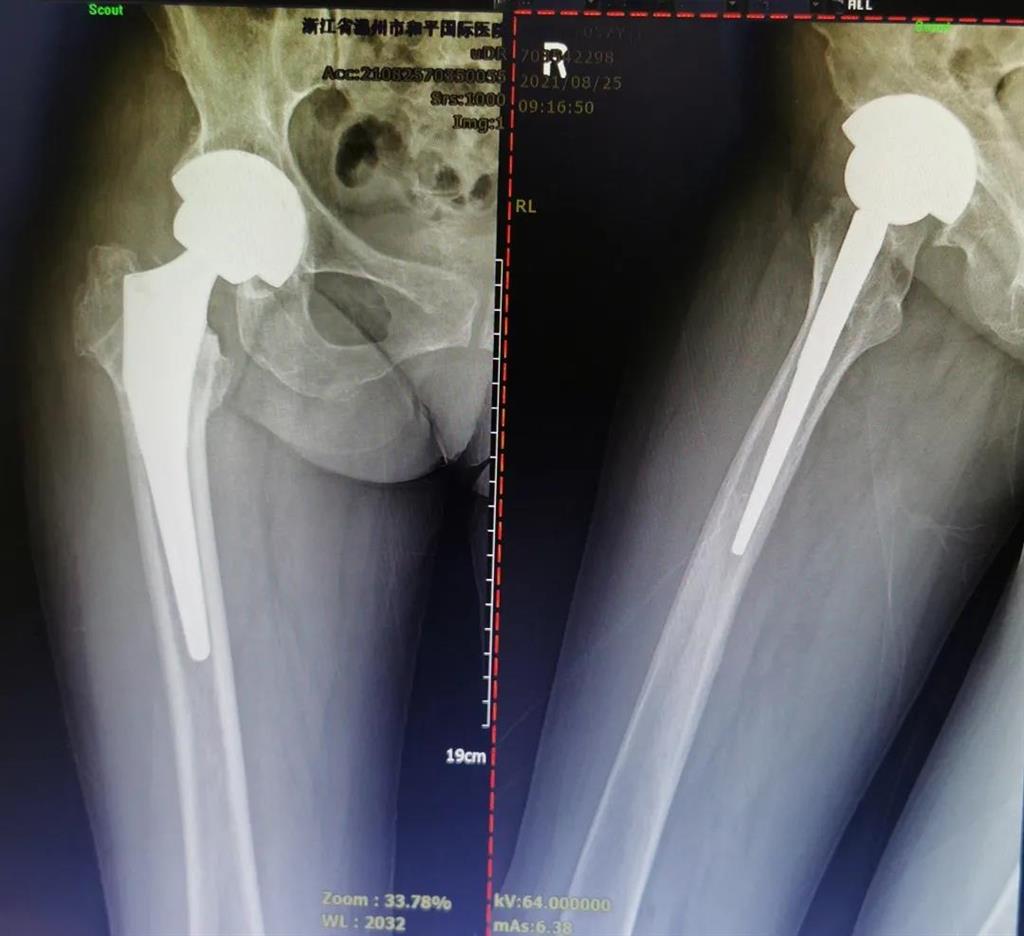

手術(shù)很成功!李女士術(shù)后第二天便可下地進(jìn)行簡單的鍛煉了。

兩個(gè)月后,李女士的腿已與常人無異,苦纏2年有余的病痛,終于徹底消散。

(△做完“右股骨頸全髖關(guān)節(jié)置換術(shù)”后的影像)